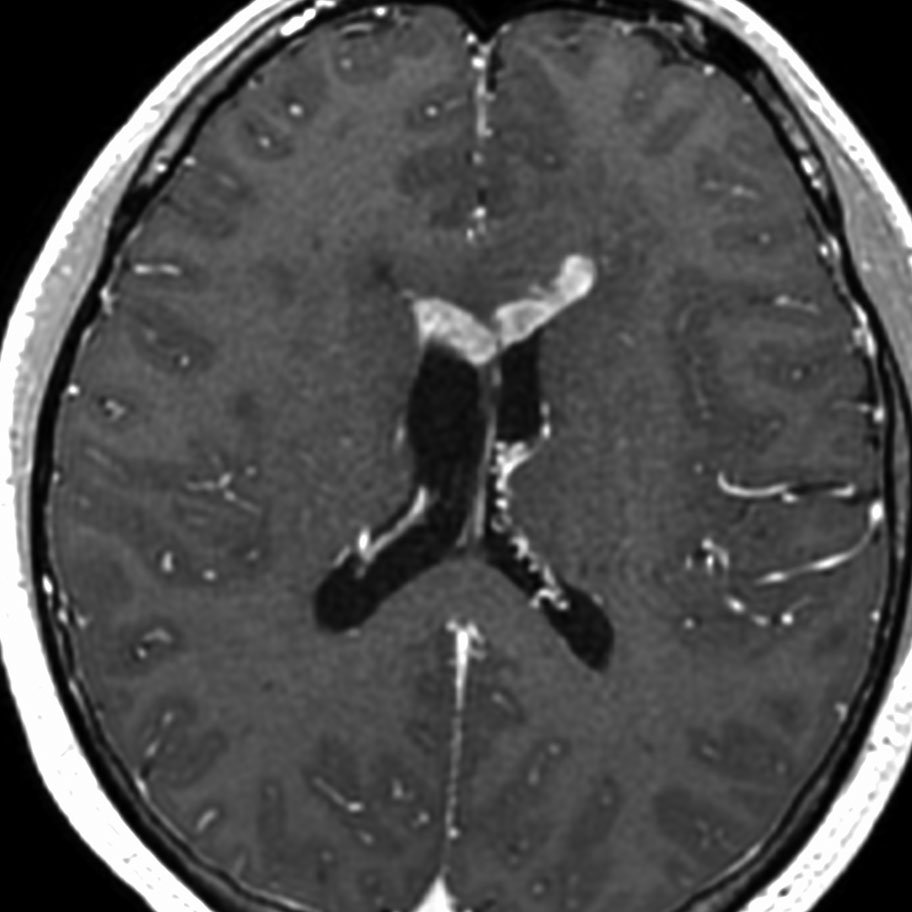

ガドリニウム増強では,前頭葉腫瘍というより,側脳室壁にベトベトくっついているような腫瘍です。germinoma特有のsubependymal infiltration像を示します。

生検後2ヶ月,セカンドオピニオンのために受診された時の画像です。腫瘍が縮小傾向にあります。入院中に行われた何度かのCT被曝の影響で,germinomaの退縮が生じたのだと判断しました。